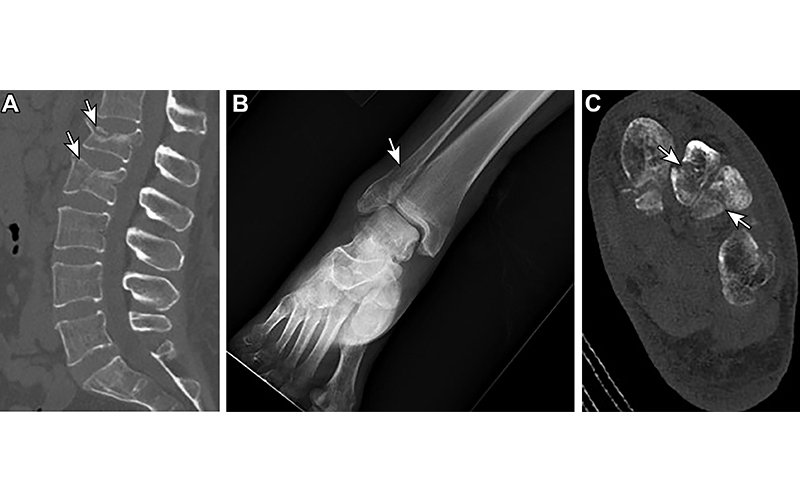

Osteoporosis and osteoporotic fractures in a 48-year-old woman with anorexia. (A) Sagittal nonenhanced CT image of the lumbar spine shows compression fractures of the L1 and L2 vertebral bodies (arrows). (B) Anteroposterior radiograph of the right ankle obtained on the same day as A shows a distal fibular fracture (arrow). (C) Axial nonenhanced CT image of the left foot confirms these fracture findings (arrows). https://doi.org/10.1148/rg.220018 © RSNA 2022

Lack of body fat may be noted on posteroanterior chest radiograph, indicated by a small heart shadow. Low bone density manifests on radiographs and CT with cortical thinning and hyperlucent bones and can lead to fragility or insufficiency fractures so subtle that they may only initially be seen on MRI. Laxity of the esophageal sphincter from repeated purging can lead to inflammation and subsequent thickening of the lower esophageal wall, a finding commonly seen in chronic reflux. While CT can demonstrate esophageal wall thickening, laxity of the lower esophageal sphincter is best demonstrated using fluoroscopy.